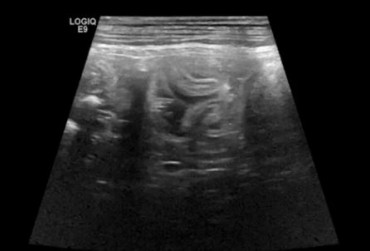

Kot syberyjski, samiec, 4l. Robaczyca jelit cienkich.

24 czerwca 2019

Wojciech Atamaniuk

Czytaj więcej